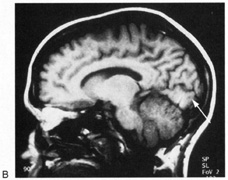

Fig. 5. Macula-splitting hemianopia. A 47-year-old man with AIDS and sudden onset of poor vision. A. Fields show complete left hemianopia. B. MRI shows lesion of right lateral occipital cortex, affecting distal optic radiations. Biopsy showed nonspecific encephalitis.

Fig. 6. Lesion of temporal optic radiation. Left superior quadrantanopia, respecting horizontal meridian (A), from infarct of right medial temporal lobe, in posterior cerebral artery territory (B). (From Rosen ES, Eustace P, Thompson HS, Cumming WJK [eds]: Neuro-Ophthalmology. London: Mosby, 1998.)